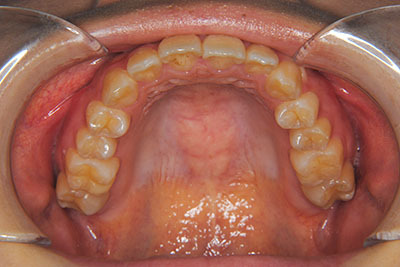

おとなの方でも矯正治療をあきらめないでください!

いくら歯が動き易くとも、本人がやる気でなければ効果は出ませんし、むし歯発生のリスクも高まります。おとなの方は顎の成長が終わっているため、治療の計画が立てやすいとも言えます。「もう大人だから…」とあきらめず、一度ご相談ください。